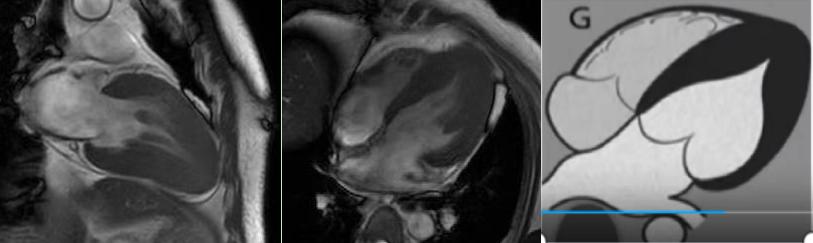

非缺血性心肌病:擴(kuò)張型心肌病、肥厚型心肌病、高血壓性心肌病、心肌淀粉樣變、心肌過(guò)度小梁化、限制性心肌病、心臟結(jié)節(jié)病、心肌炎等,心肌呈現(xiàn)不同程度條狀、斑片狀、斑點(diǎn)狀的延遲強(qiáng)化。

擴(kuò)張型心肌病

肥厚型心肌病,舒張末期心尖形似“黑桃A征”